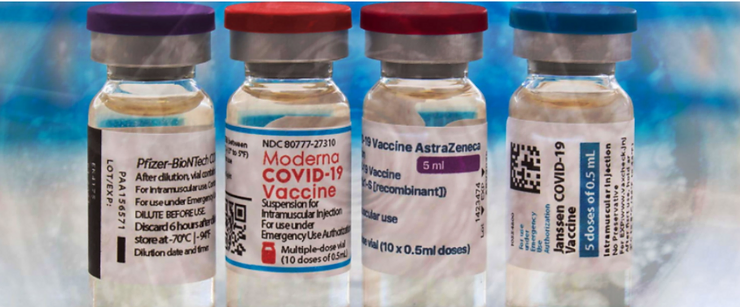

What Are The Non-disclosed Ingredients In The COVID – 19 VAXXXines?

Newsbreak 133: Team of Scientists Confirm Presence of Toxins Graphene, Aluminium, Cadmium Selenide, Stainless Steel, LNP-GO Capsids, Parasites, Other Toxins Variously in 4 COVID Vaccines: Pfizer, Moderna, AstraZeneca, Johnson & Johnson

https://everydayconcerned.net/2021/08/28/newsbreak-133-team-of-scientists-confirm-presence-of-toxins-graphene-aluminium-cadmium-selenide-stainless-steel-lnp-go-capsids-parasites-other-toxins-variously-in-4-covid-vaccines-pfizer-mode/